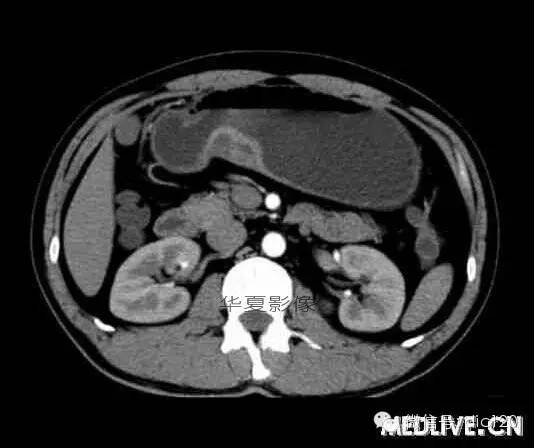

男,36歲,間斷性返酸噯氣3年,3個月前出現(xiàn)上腹疼痛,饑餓時加重。圖1-3為CT平掃,圖4-6分別為CT增強(qiáng)掃描的動脈期、門脈期和延遲期。

CT檢查可見胃幽門前區(qū)胃小彎側(cè)胃壁局限性增厚、隆起或伴凸向胃腔內(nèi)的小結(jié)節(jié)灶,寬基地,境界光整,注射對比劑,增強(qiáng)掃描后,CT值可達(dá)50HU以上,與正常胰腺強(qiáng)化相仿。

胃迷走胰腺大多位在距幽門1-6cm的胃竇胃大彎側(cè),粘膜下層內(nèi),為1-3cm大小的病灶。 與胃壁以寬基底相,增強(qiáng)掃描病灶表面覆蓋的黏膜明顯強(qiáng)化且連續(xù),病灶內(nèi)無明顯壞死,病變強(qiáng)化方式類似于正常胰腺組織;當(dāng)病灶出現(xiàn)邊緣臍凹征或中央導(dǎo)管征時,對EP的診斷具有一定的特異性。